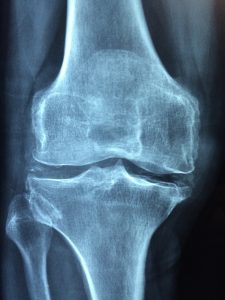

Gonarthrose chez les sujets âgés

Indications des prothèses de genou p. 103

Indications des prothèses de genou La gonarthrose est la localisation la plus fréquente de la maladie arthrosique : on considère sa prévalence aux alentours de 60 % au-delà de 65…